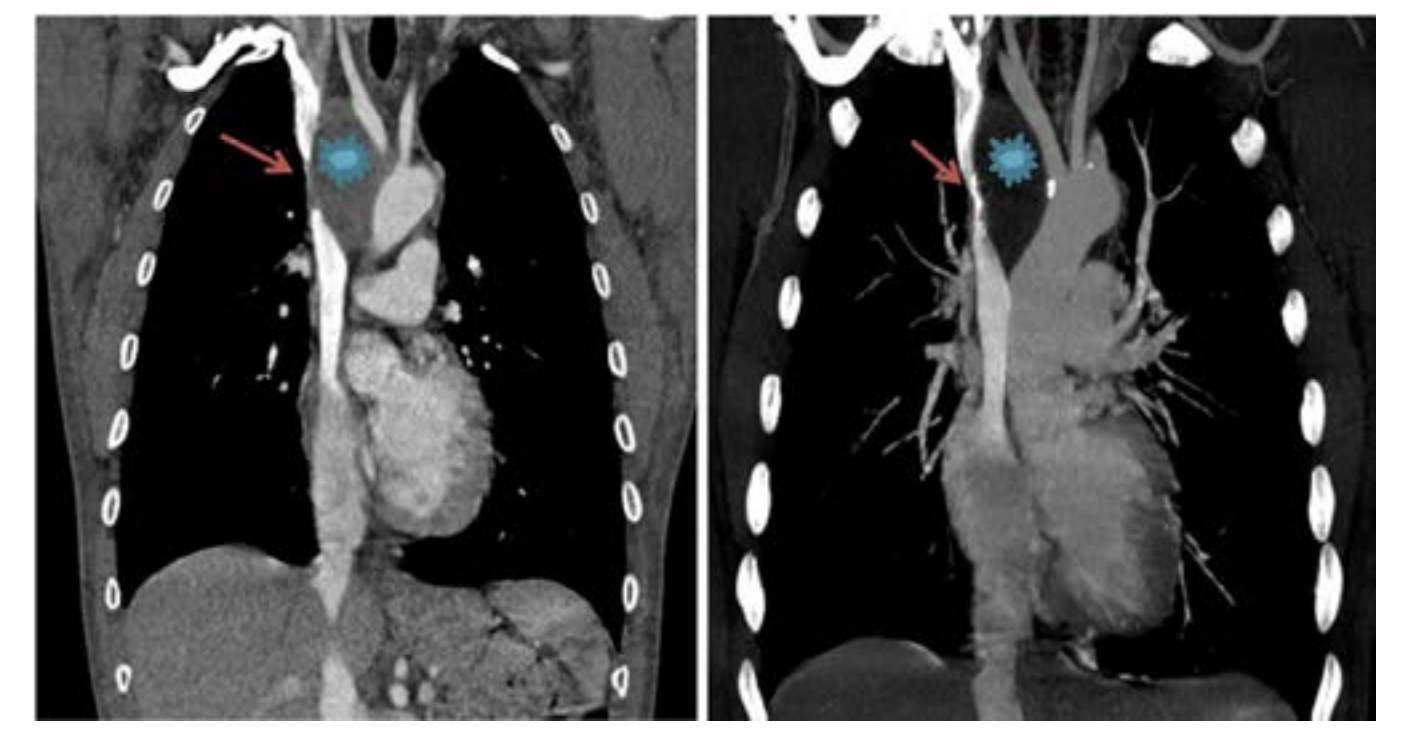

The caval stenosis, in the series, was diagnosed by means of an angio CT scan of the chest, followed by confirmation using the venacavogram.

In what concerns the place of imaging exploration, the majority of authors believe that CT-scan with its high-quality multiplanar reconstructions is a crucial imaging tool. In fact, angio-CT scan confirms the diagnosis, determines the exact extent of obstruction, the nature and the degree of vena cava obstruction as well as it orients the placement of the endoprosthesis and the presence of associated pathologies.6 A venographic classification according to Stanford and Doty was set. Four Patterns of venous collateral return have been described.5 The 4th one matches with the most severe in terms of clinical symptoms (Schema 1).